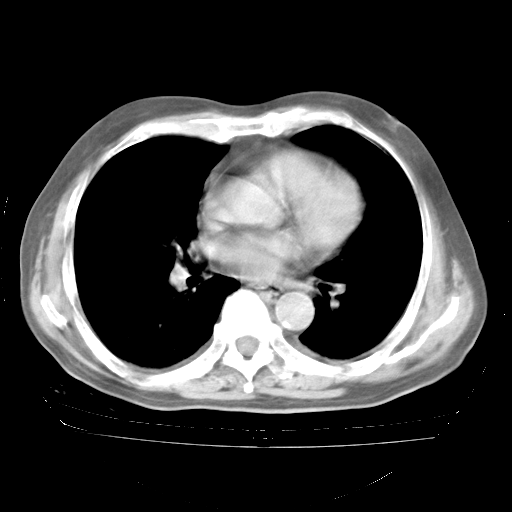

4月28日肺部CT——再次出现类似去年5月9日——透光度降低,“间质性”改变。